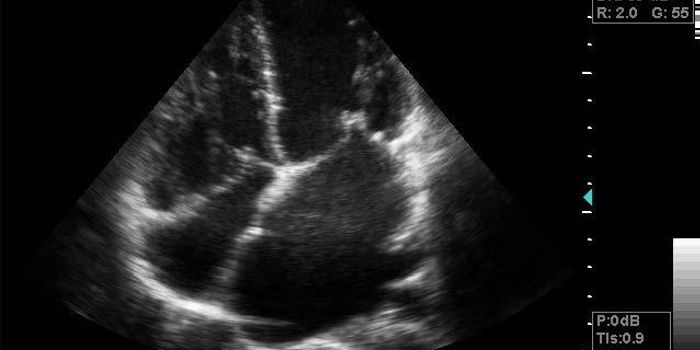

Cardiology is an ever-evolving branch of medicine concerned with disease and disorders of the heart. Cardiology trending provides articles and resources to keep you informed on risk factors, causes and prevention of heart disease, evidence-based research and advances in treatment.